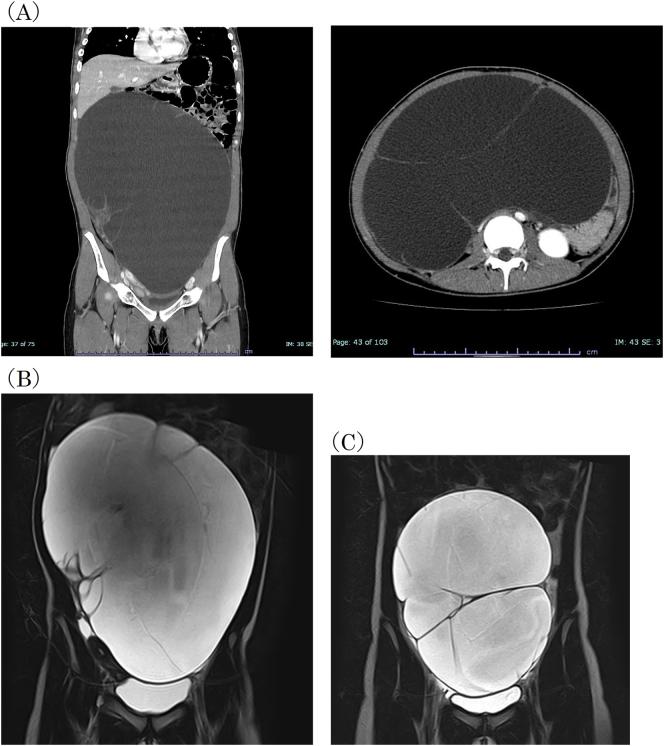

A 13-year-old patient, with a sizable ovarian tumor underwent laparoscopic-assisted cystectomy. On histopathology, the tumor was diagnosed to be an ovarian mucinous cystadenoma. The mucinous cystadenoma recurred 13 months after surgery and subsequently laparoscopic right adnexectomy was performed.

一名13岁患者,患有较大的卵巢肿瘤,接受了腹腔镜辅助囊肿切除术。组织病理学检查显示,该肿瘤被诊断为卵巢黏液性囊腺瘤。黏液性囊腺瘤在术后13个月复发,随后进行了腹腔镜右侧附件切除术。